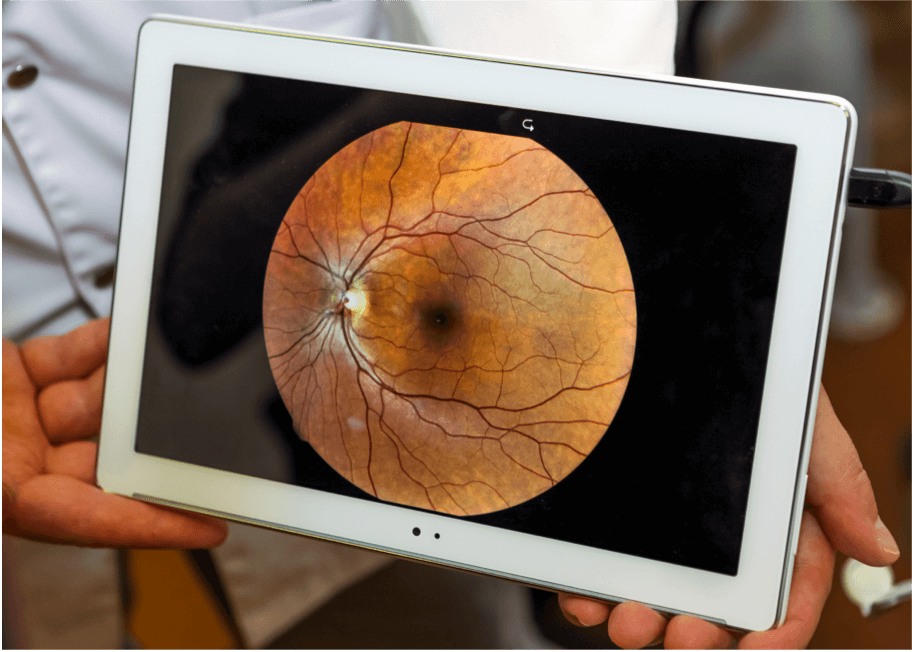

Fundusfotografie

Die Fundusfotografie wird mit einem Mikroskop bei geringer Leistungsstufe durchgeführt, um Farbbilder der Netzhaut aufzunehmen.7 Sie wird häufig zur Diagnose der AMD verwendet, da sie Netzhautanomalien wie Drusen, Pigmentstörungen, Atrophie, Blutungen und Flüssigkeitsansammlungen sichtbar macht.7 Die im Laufe der Zeit aufgenommenen Bilder können miteinander verglichen werden, um das Fortschreiten der Krankheit zu überwachen.